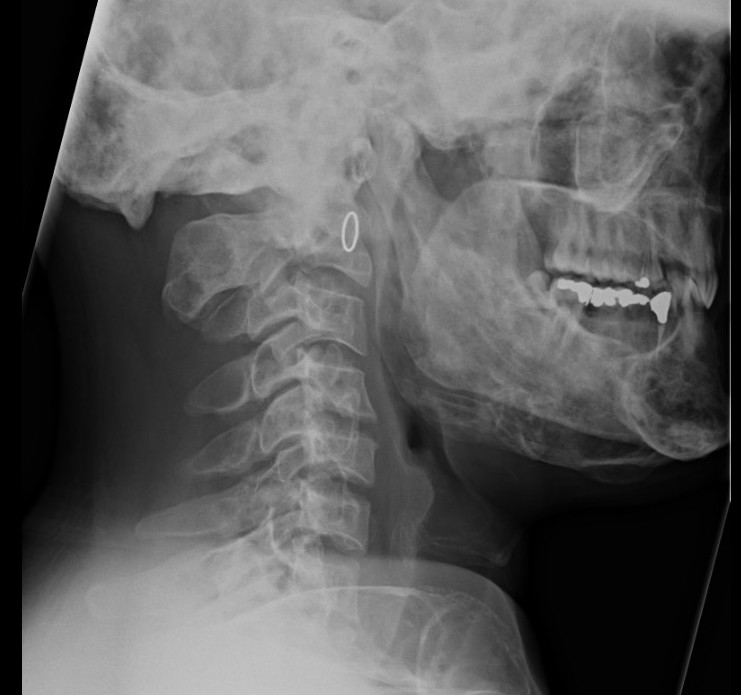

Craniofacial involvment

- slow growing painless masses

- cosmetic deformity / dental problems / vision and hearing loss

Intramedullary lucent diaphyseal lesion with 'ground glass appearance'

- thinned, slightly bulged cortex

- ± endosteal scalloping